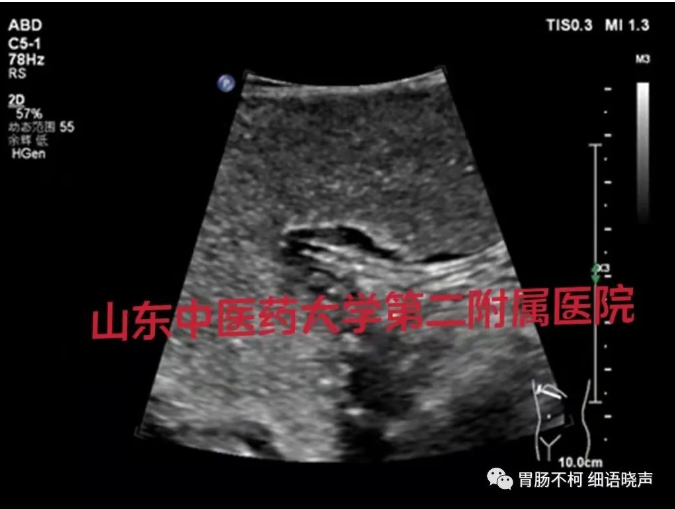

病例一,胃体前壁胃壁增厚性病变: